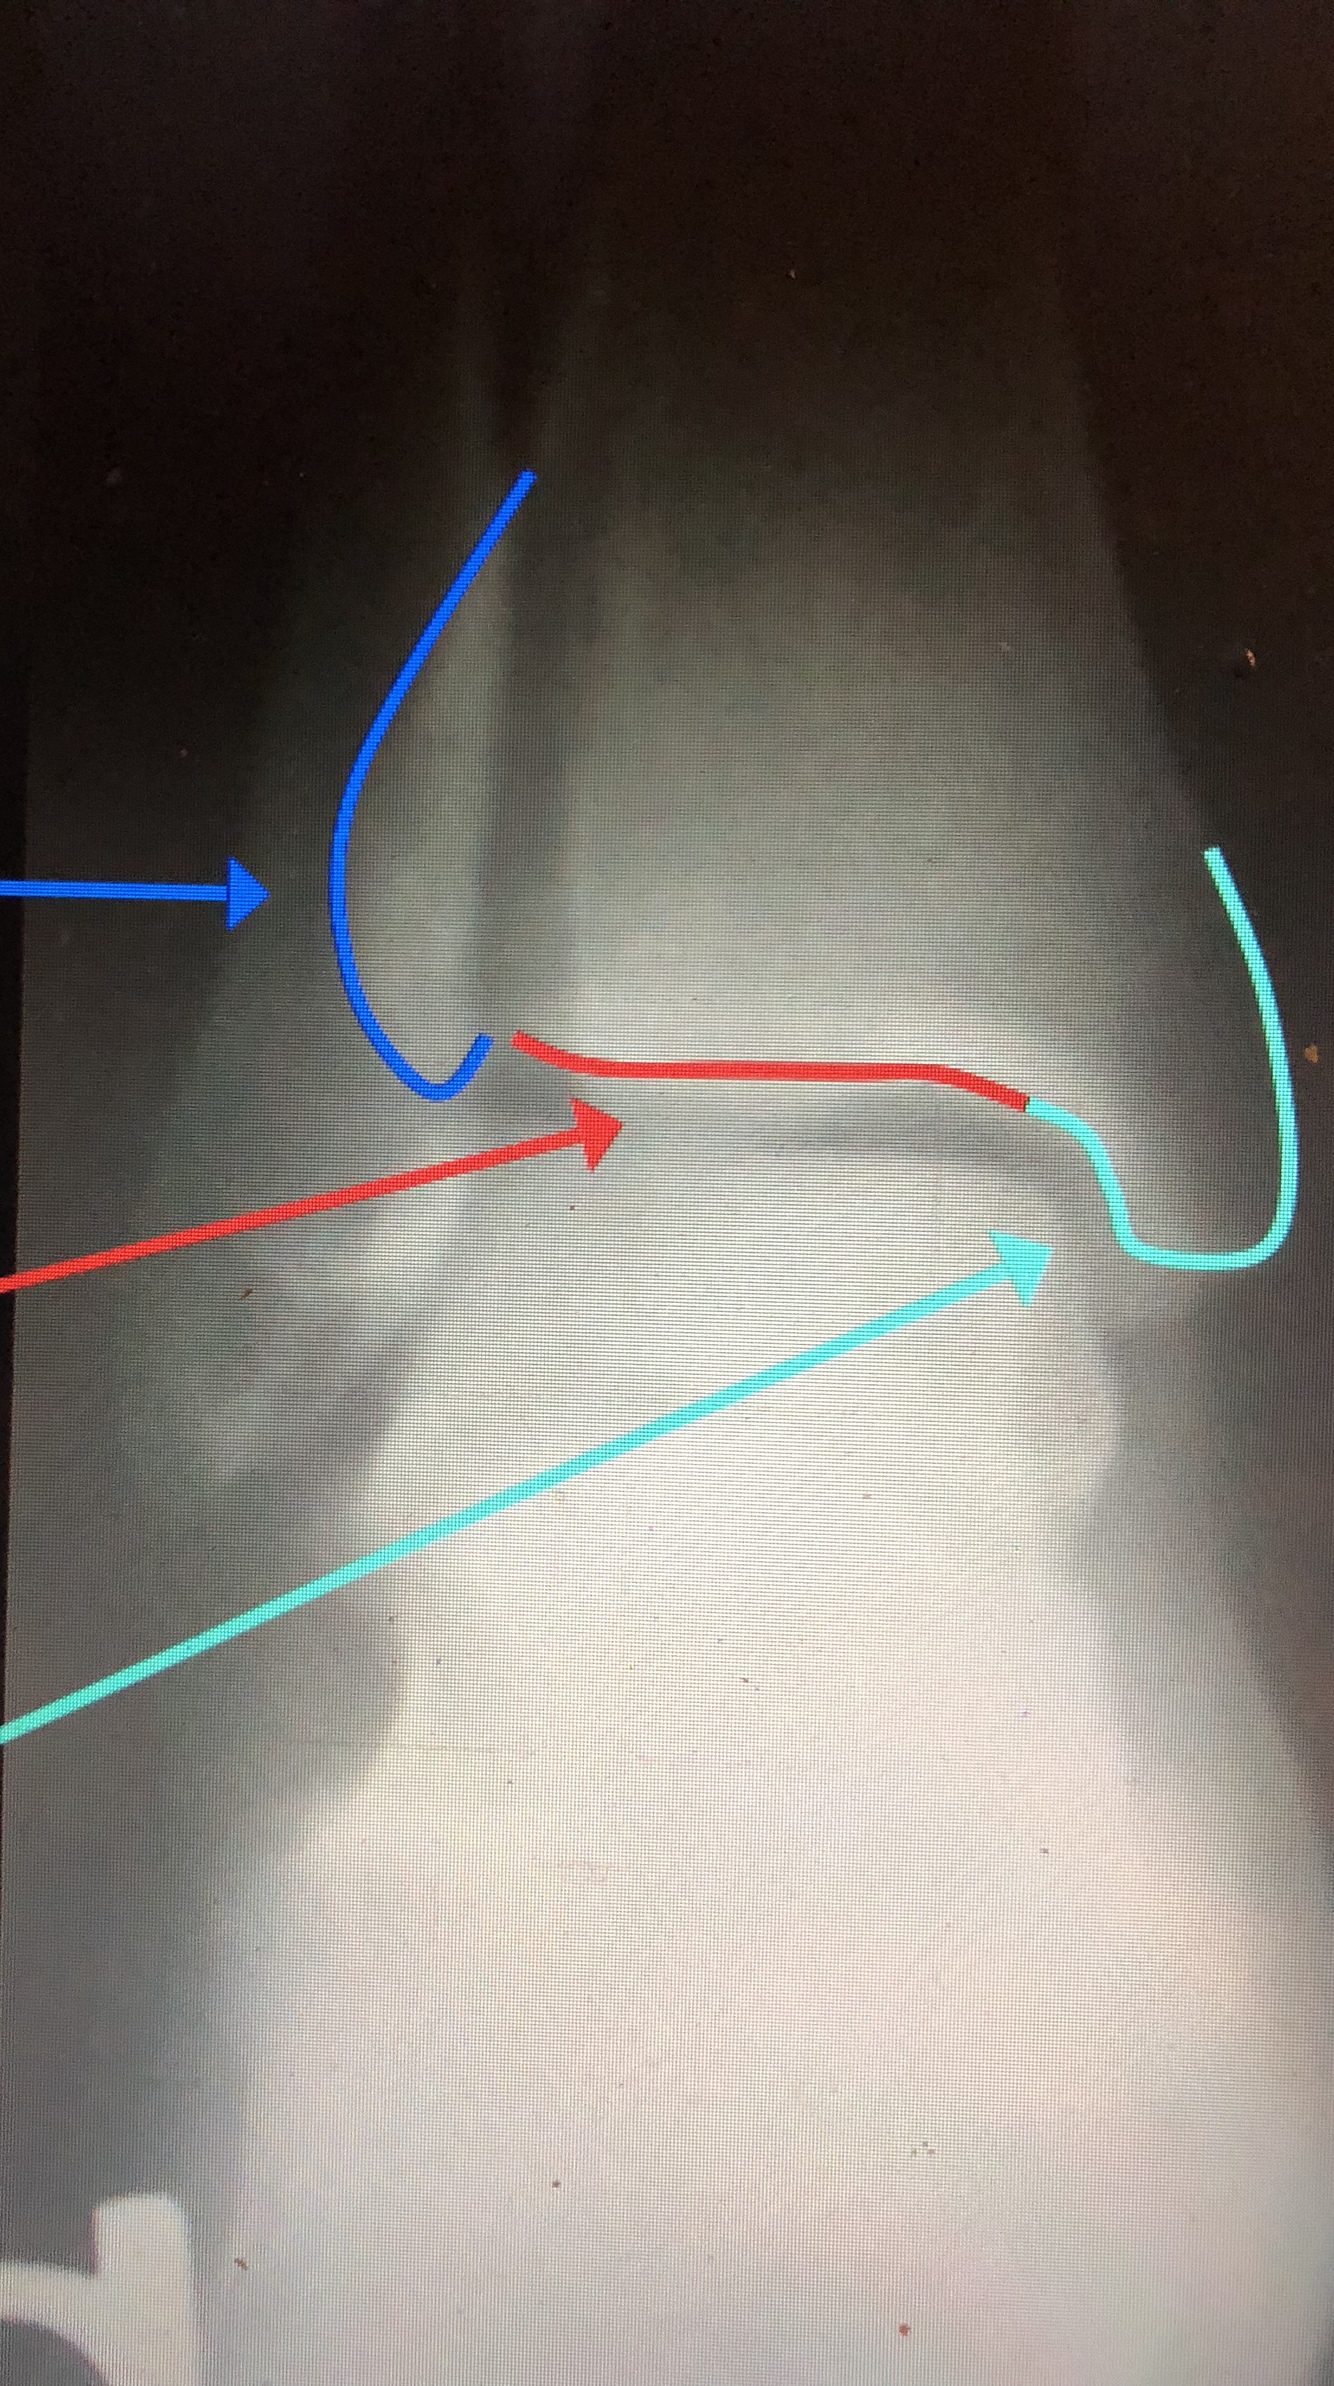

What is the dark blue line?

Lateral margin of the Tibia

What is the red line?

Plafond

What is the light blue line?

Medial Malleolus